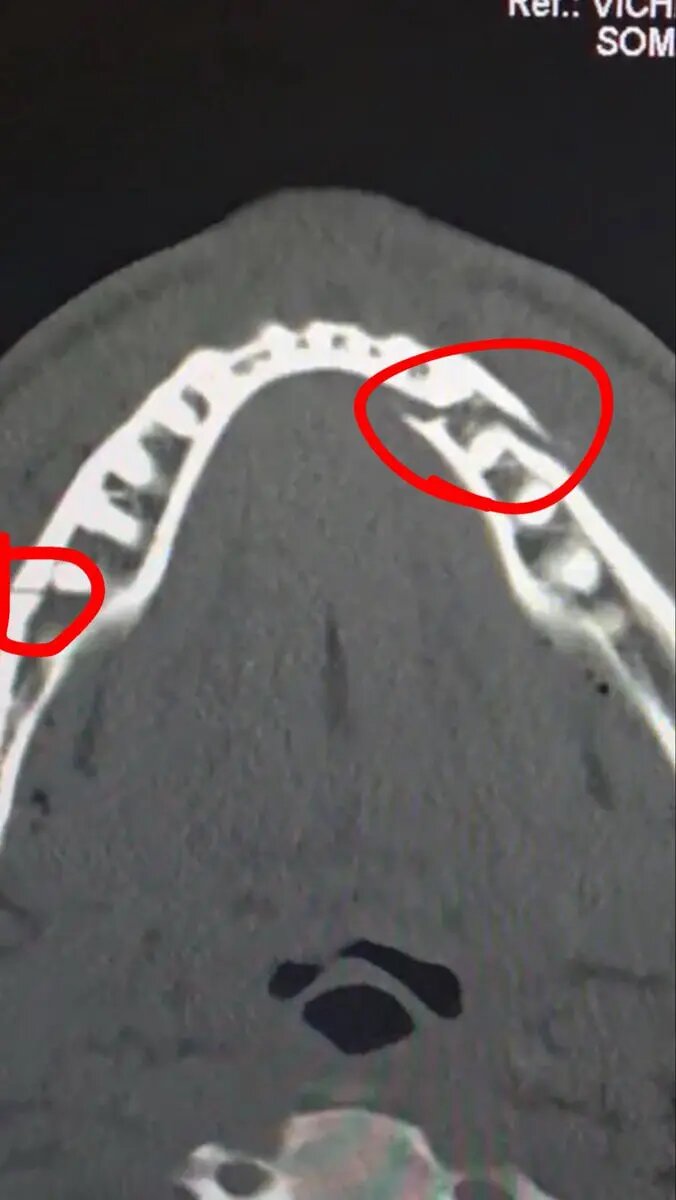

در این مبارزه، جاشوا در راندهای پنجم و ششم دو بار پاول را نقش زمین کرد و در نهایت بوکسور آمریکایی نتوانست پیش از پایان شمارش داور به مبارزه بازگردد. پاول پس از این شکست، تصویری از عکس رادیولوژی فک خود را در شبکه اجتماعی «ایکس» منتشر کرد و نوشت: «شکست از دو ناحیه در فک. ده روز دیگر کانلو(بوکسور حرفهای مکزیکی) را به من بدهید.»

به دلیل این آسیبدیدگی، پاول در نشست خبری پس از مبارزه حضور پیدا نکرد. با این حال، نکیسا بیداریان، مدیرعامل شرکت Most Valuable Promotions (پروموتر پاول)، در اینباره گفت: «حال او خوب است. خودش رانندگی کرد و به بیمارستان رفت. شکستگی فک در ورزش، بهویژه در بوکس و MMA، اتفاقی رایج است. بر اساس نظر پزشکان و جراحانی که با آنها صحبت کردهایم، دوره نقاهت بین چهار تا شش هفته خواهد بود.»